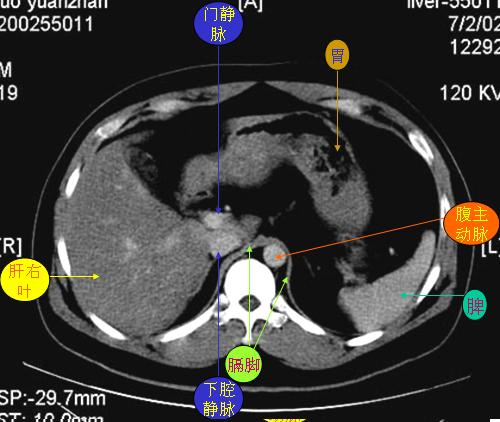

腹部ct解剖与基本病变